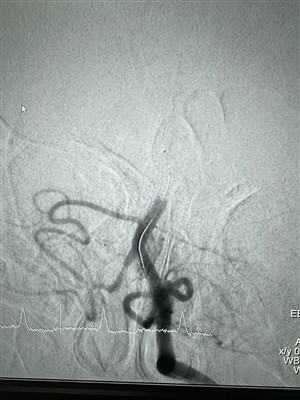

กรณีการใช้งานระบบอุดหลอดเลือดด้วยของเหลว LAVAแบ่งปันการผ่าตัดแทรกแซงล่าสุดที่เสร็จสิ้นโดยใช้ระบบ LAVA Liquid Embolic ของ NeuroSafe

เพิ่มเติม -